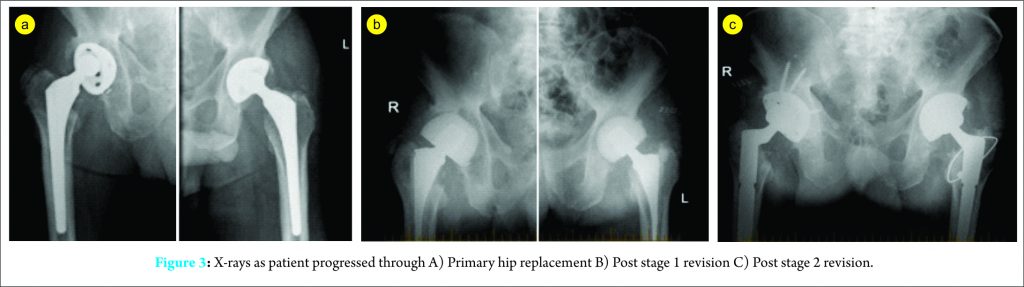

The patient received a period of inpatient rehabilitation and was discharged 13 days after surgery. Upon follow-up at six months, he remained clinically well and was mobilizing with two crutches. Pathology results were also unremarkable with normal infective and inflammatory markers. Image 3 shows the X-rays as the patient progressed through the various stages.